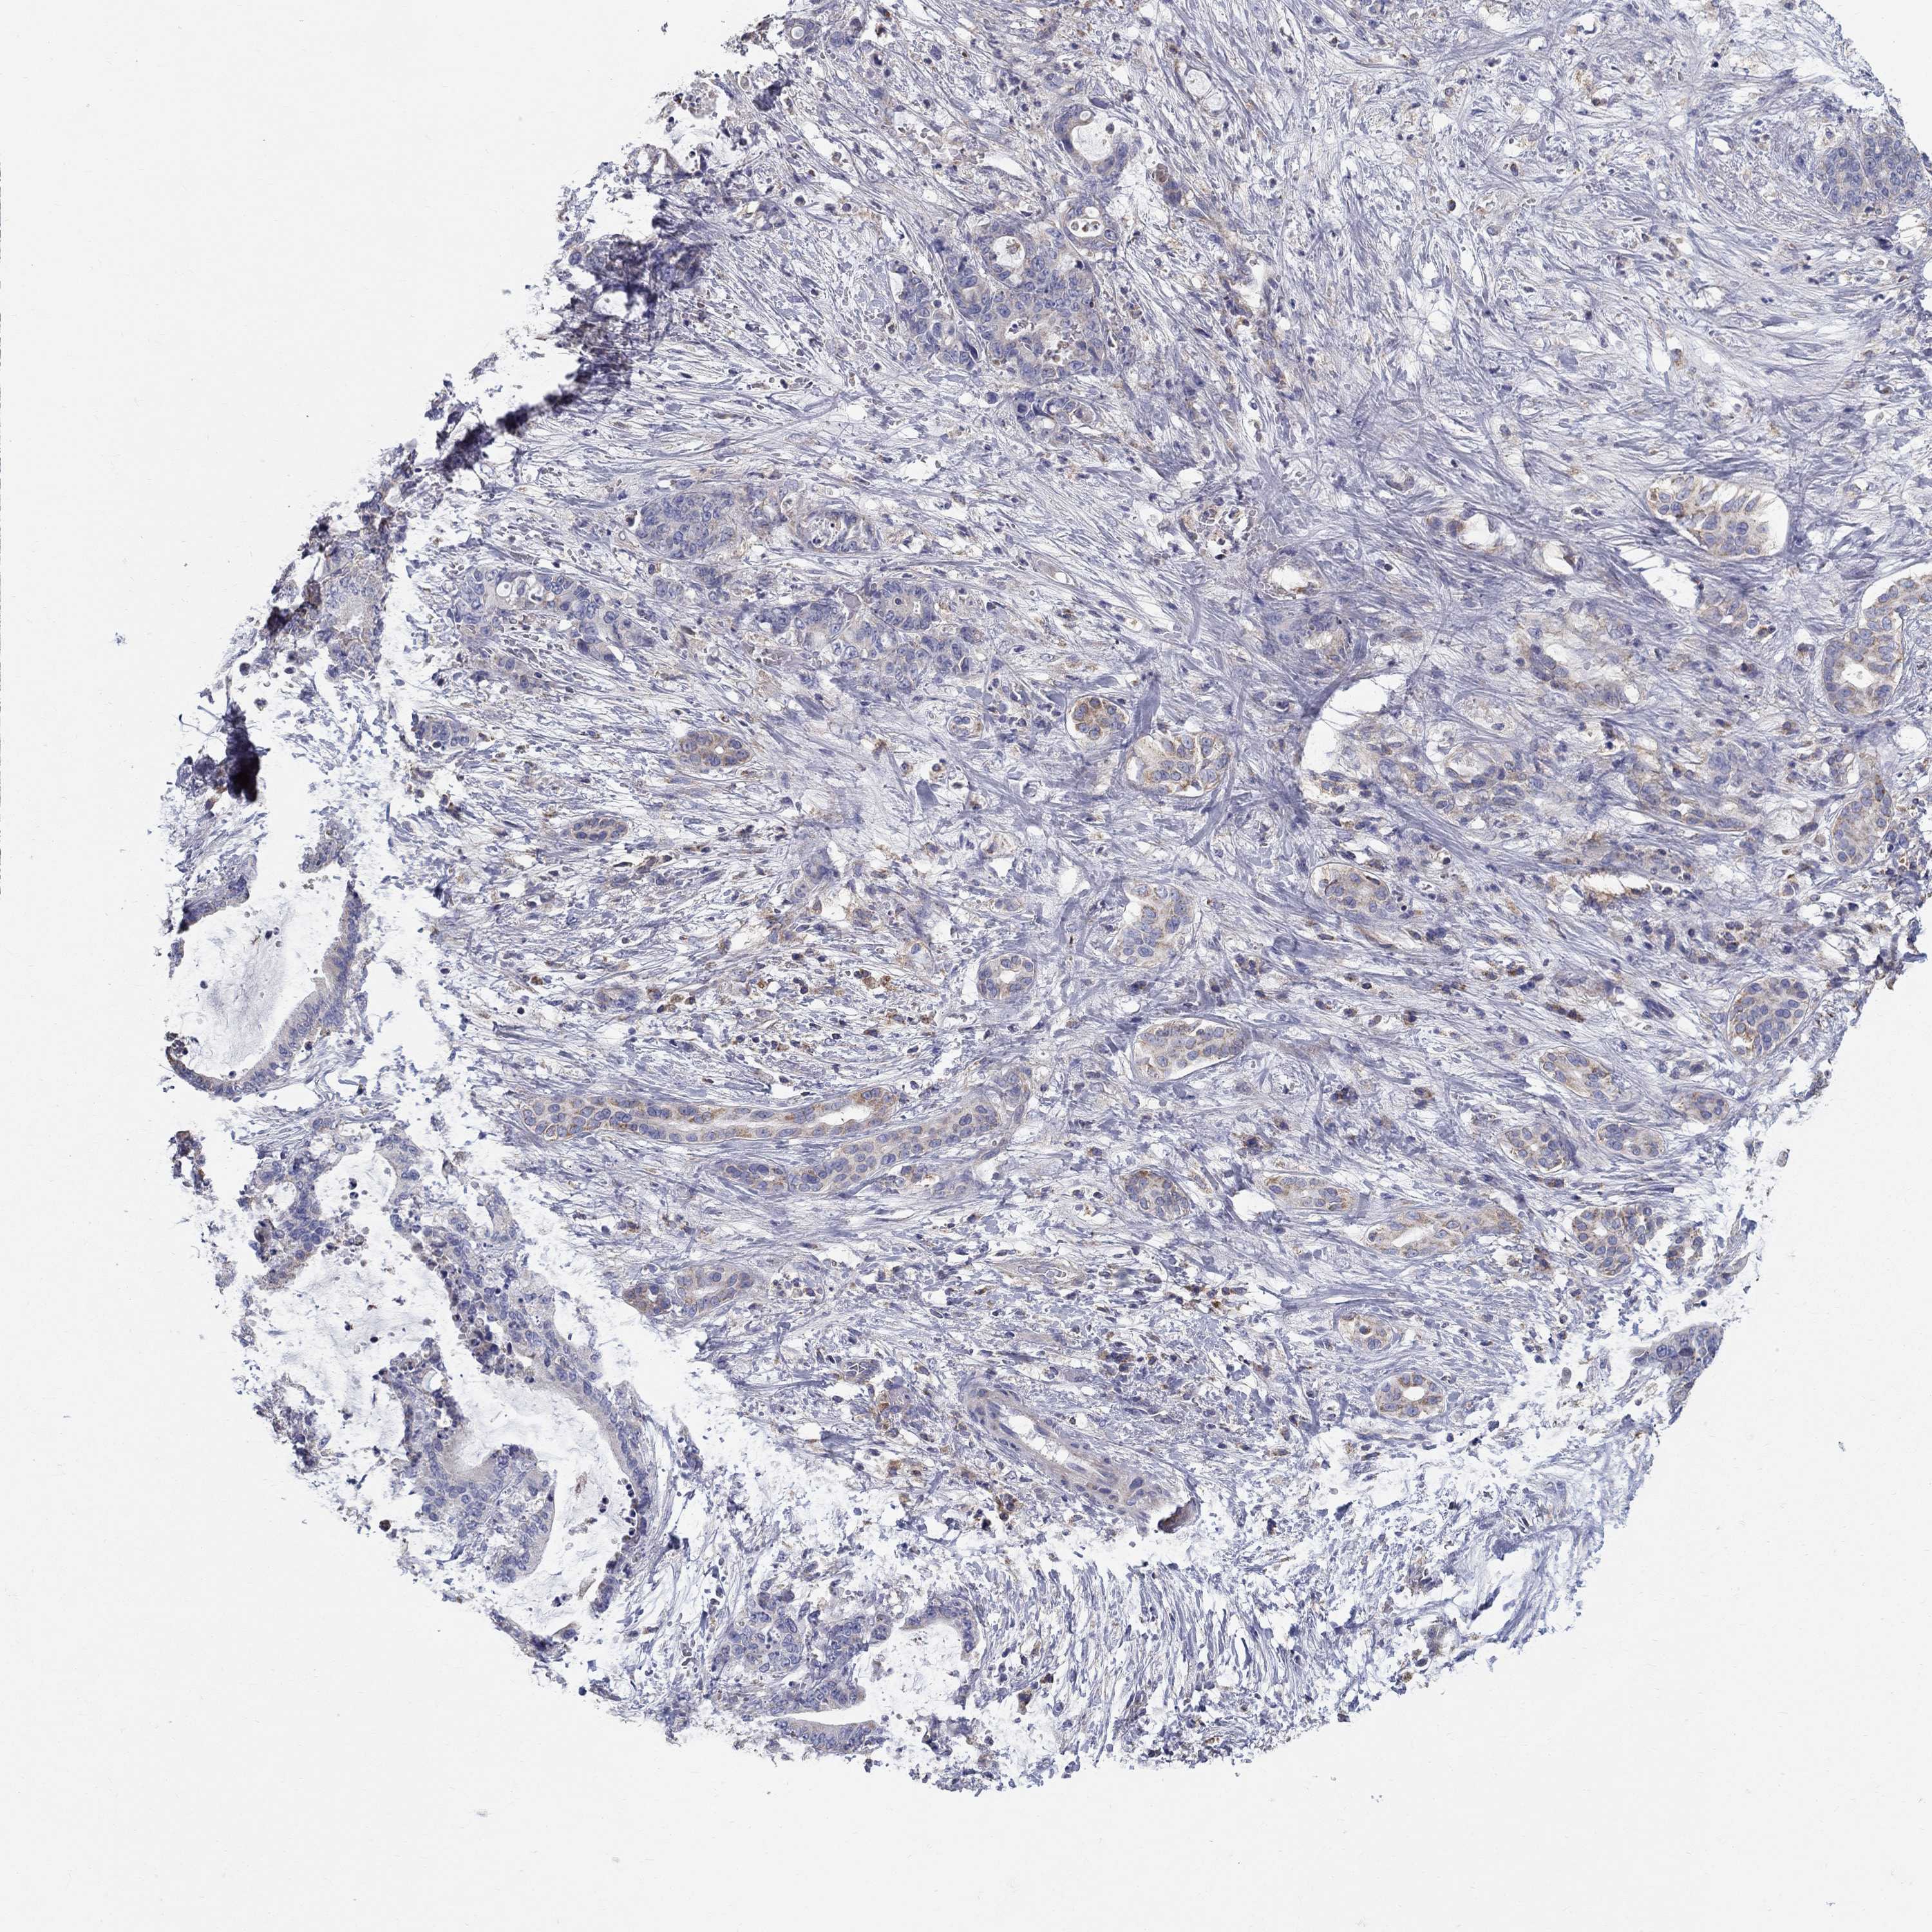

LIVER CANCER - Protein expressioni

A mouse-over function shows sample information and annotation data. Click on an image to view it in a full screen mode. Samples can be filtered based on level of antibody staining by selecting one or several of the following categories: high, medium, low and not detected. The assay and annotation is described here.

Note that samples used for immunohistochemistry by the Human Protein Atlas do not correspond to samples in the TCGA dataset.

Antibody stainingi

Antibody staining in the annotated cell types in the current human tissue is reported as not detected, low, medium, or high, based on conventional immunohistochemistry profiling in selected tissues. This score is based on the combination of the staining intensity and fraction of stained cells.

Each image is clickable and will lead to virtual microscopy that enables deeper exploration of all samples and also displays staining intensity scores, fraction scores and subcellular localization as well as patient and tissue information for each sample.

Antibody HPA044555

Antibody HPA058103

Staining

High

Medium

Low

Not detected

Intensity

Strong

Moderate

Weak

Negative

Quantity

>75%

75%-25%

<25%

None

Location

Nuclear

Cytoplasmic/membranous

Cytoplasmic/membranous,nuclear

Cholangiocarcinoma

Carcinoma, Hepatocellular, NOS